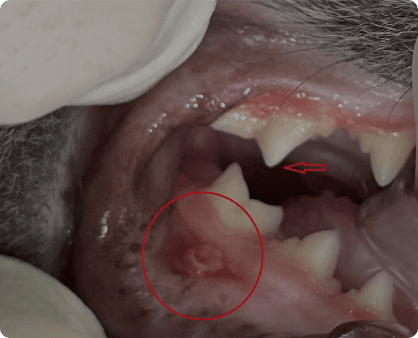

치태, 치석 등에 존재하는 구강 세균에 대한

면역 반응으로 고양이 구강에서 심한 구내염이 발생하거나,

치아가 흡수되어 파괴되는 심한 소모성 질환

외상, 중증 치주염에 의해 턱 뼈가 골절되는 상태.

특히 하악 전치부 결합부의 분리가 흔하게 관찰된다.